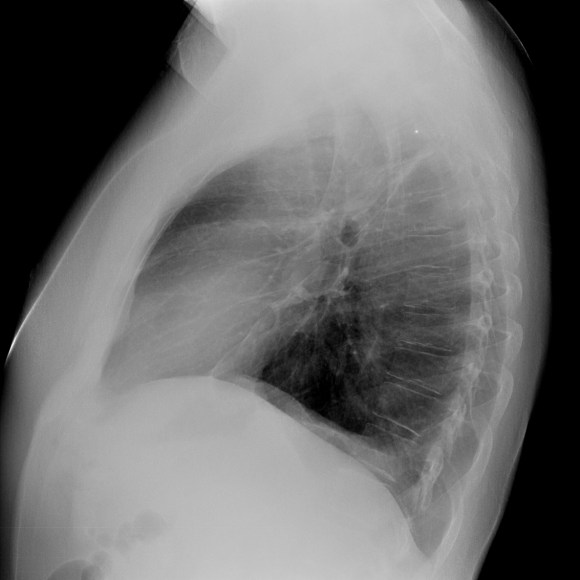

- Prótesis mamaria izquierda (obsevar el aumento de densidad homogéneo y de bordes bien definidos en la placa PA y lateral)

- Parénquimas pulmonares y silueta cardiomediastínica sin alteraciones significativas.